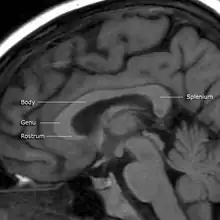

A number of separate nerve tracts, classed as subregions of the corpus callosum, connect different parts of the hemispheres. The main ones are known as the genu, the rostrum, the trunk or body, and the splenium.[4]

The corpus callosum has four main parts – individual nerve tracts that connect different parts of the hemispheres. These are the rostrum, the genu, the trunk or body, and the splenium.[4] Fibres from the trunk and the splenium, known together as the tapetum ("carpet"), form the roof of each lateral ventricle.[6]

The front part of the corpus callosum, towards the frontal lobes, is called the genu ("knee"). The genu curves downward and backward in front of the septum pellucidum, diminishing greatly in thickness. The lower, much thinner part is the rostrum and is connected below with the lamina terminalis, which stretches from the interventricular foramina to the recess at the base of the optic stalk. The rostrum is named for its resemblance to a bird's beak.

The end part of the corpus callosum, towards the cerebellum, is called the splenium. This is the thickest part, and overlaps the tela choroidea of the third ventricle and the midbrain, and ends in a thick, convex, free border. Splenium translates as "bandage" in Greek.

The trunk of the corpus callosum lies between the splenium and the genu.